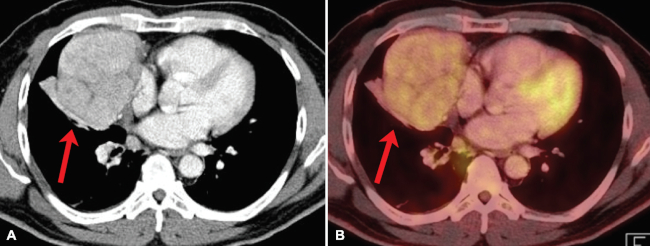

Linfoma

El linfoma es la causa más frecuente de masa mediastínica prevascular en niños y adultos jóvenes.20 El compromiso tímico en linfoma ocurre en general en el contexto de enfermedad diseminada, pero ocasionalmente puede verse compromiso aislado del timo. En las imágenes puede ser difícil de distinguir de otras masas tímicas. En TC, puede aparecer como aumento de volumen difuso, una masa dominante o múltiples masas separadas.13 Una apariencia más sugerente es la de un aumento de volumen tímico nodular y asimétrico. La presencia de una masa de esas características en un paciente joven asociado a adenopatías orienta al diagnóstico. En PET-CT se reconocen hallazgos similares, asociados a incrementos de SUVmáx, generalmente sobre 3,4 (►Fig. 7). Se considera que el valor de SUVmáx es predictivo de agresividad: los valores mayores a 13 sugieren linfomas agresivos y los menores a 6, linfomas indolentes.21